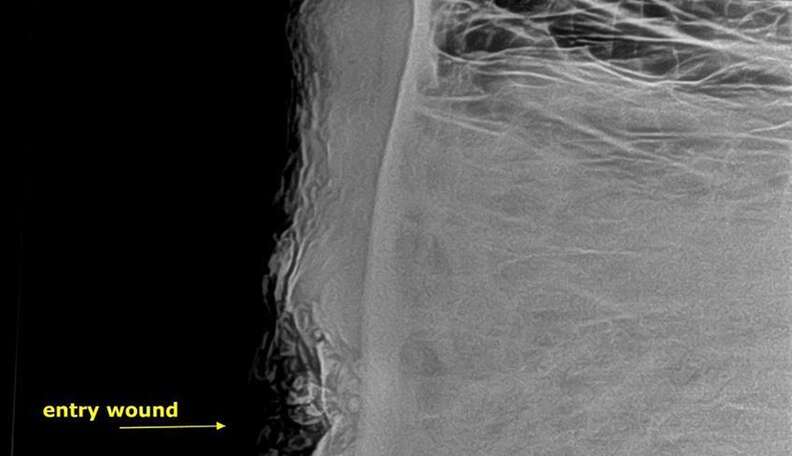

The elephant was tranquilized and then taken in for an X-ray, which showed a deformed bullet present inside of his head.

Such was the case with Pretty Boy, who was hit just centimeters too high for a "kill shot." Instead, the bullet glanced off his skull and caused a fracture in the bones of his sinuses. Furthermore, his head wound was infected. "It was essential to remove the dead pieces of bone so that the body could continue to heal the infection," Marabini said.